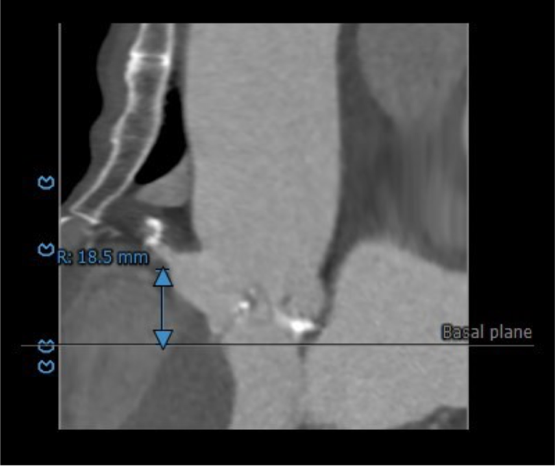

主动脉根部评估:

患者为79岁男性,术前超声心动图提示三叶式主动脉瓣重度狭窄伴中度关闭不全、瓣叶明显钙化增厚、峰值流速 3.63m/s、平均跨瓣压差 33mmHg、有效瓣口面积 0.9cm²;左心扩大,室间隔增厚;二尖瓣中轻度反流、三尖瓣轻度反流;LVEDd:59mm,LVEF:53%。